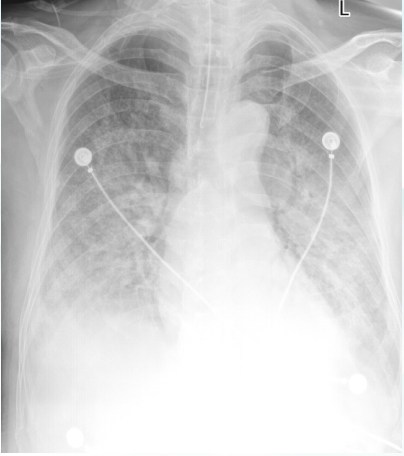

7. 影像学及超声检查

胸部CT2025-02-08(图1):双肺见大片状磨玻璃、实变影,以双肺下叶及左肺上叶明显,内见空气支气管征象,边缘模糊,考虑感染性病变可能,伴间质受累,合并其他待排双肺上叶少许小结节,多系炎性双肺少许小肺大泡。双侧胸腔少量积液,双侧胸膜增厚粘连心包少量积液可能主动脉壁及主动脉瓣区钙化纵隔及双肺门淋巴结增多、部分稍增大,部分伴钙化。扫及胸段食管稍扩张。

图片

1  患者胸部CT(2025-02-08)

床旁胸片2025-02-11:双肺纹理增多、模糊,双肺透亮度减低,见大片状密度增高影,考虑感染可能。双侧肋隔角显示不清,胸腔积液(图2)

2  患者入院后胸部X线片(2025-02-11)